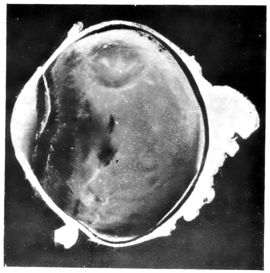

PLATE III.

16.

ABUNDANT EXUDATE INTO VITREOUS CAVITY

curly bracket span

42

17.

LENS FIRMLY FIXED BY ORGANIZED EXUDATE

18.

LENS FIRMLY FIXED BY ORGANIZED EXUDATE, BUT IN UNUSUAL POSITION

19.

TOTAL DETACHMENT OF RETINA, WITH CYST FORMATION

20.

RECLINED LENS LYING IN FRONT OF THE HYALOID BODY

21.

RECLINED LENS LYING IN FRONT OF THE HYALOID BODYxii